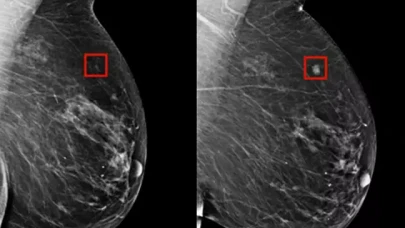

Yapay zeka, kanseri 4 yıl önceden tespit etti